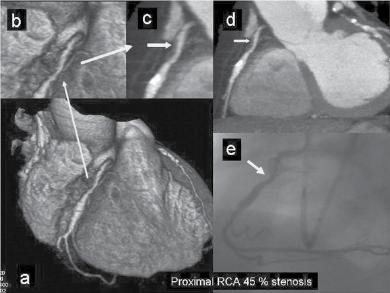

Figure 1.1 (A) Normal case: coronary angiography (left) and three‐dimensional CTA (right) showing normal left anterior descending (LAD, arrow) and left circumflex (LCX) coronary arteries. The latter is partially covered by the left appendix in CTA. (B) Normal case: coronary angiography (left) and CTA (right) showing a normal dominant right coronary artery (RCA). (C) An 85‐year‐old man with atypical chest pain: (a) Maximal intensity projection (MIP) of CTA with tight mid‐LAD stenosis that correlates perfectly with coronary angiography (b). (D) Similar case as (C) but with the stenosis in the proximal RCA. (a–d) CTA and (e) coronary angiography. (E) A patient with tight stenosis in the LCX before a bifurcation. (a) and (b) CTA and (c) coronary angiography. (F) These images show that CTA may also demonstrate the presence of stenosis in distal vessel branches, in this case in the posterior descending branch of the RCA. (a–b) CTA and (c) coronary angiography. (G) These images show that CTA (a, b) may delineate the length of a total occlusion and visualize the distal branches (see arrows in (b)). Collateral flow from the LAD to the RCA may be better visualized with CTA than with conventional coronary angiography (c: here only the RCA is shown). (H) A 42‐year‐old patient with a stent implanted in the LAD six months before. The patient complained of atypical chest pain and underwent CTA. The MIP images of CTA (a–c) show no significant restenosis, but some plaque formation in the left main trunk (d, circle) that was not well seen in coronary angiography (e). The degree of luminal obstruction by the plaque can be exactly measured by intravascular ultrasound (IVUS) (f). The ECG showed mildly inverted T waves in V1–V3 during follow‐up (see Plate 1 in color plates).